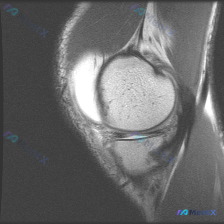

提供的影像分析:这是一张肩关节MRI T2序列冠状位图像

影像可见表现:

- 肱骨头与关节盂对位正常,肩峰形态可观察,未见明显骨髓水肿或骨质破坏

- 冈上肌腱走行于图像上方,肱骨大结节附着区域可见信号异常,肌腹信号形态基本正常,无明显严重脂肪萎缩

- 肩峰下区域可见明显液体样高信号填充,符合肩峰下-三角肌下滑囊积液

- 冈上肌腱肱骨附着点局部形态改变,异常高信号累及肌腱内部及下方,提示肌腱结构连续性受影响